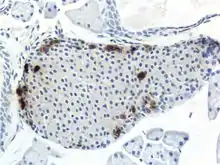

Pancreatic Islets